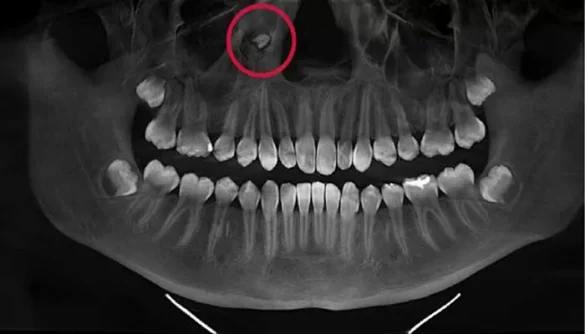

Diagnosing extra wisdom teeth begins with a comprehensive dental exam. During the examination, a dentist will check for signs of impacted or extra teeth and evaluate any symptoms the patient may be experiencing. X-rays are commonly used to get a detailed view of the teeth beneath the surface of the gums, allowing the dentist to identify extra wisdom teeth or any potential issues with alignment.

In some cases, an orthodontist or oral surgeon may be consulted to assess the position of the extra teeth and determine the best course of action. If the extra wisdom teeth are causing pain, infection, or misalignment of other teeth, removal may be necessary.